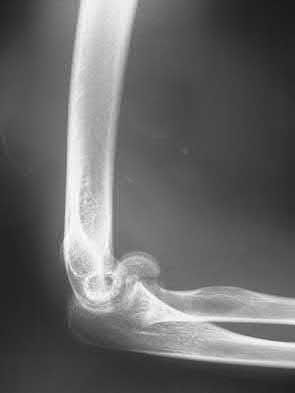

Fragment excision and triceps reattachment is ideally indicated for which of the following situations?

- A 30-year-old woman with a closed comminuted fracture involving more than 50% of the joint surface

- A 30-year-old woman with an open transverse olecranon fracture that is proximal to the trochlear notch

- A 55-year-old woman with an oblique olecranon fracture through the coronoid process

- A 75-year-old woman with an oblique fracture through the coronoid process

-

An 85-year-old man with a comminuted fracture involving less than 50% of the proximal joint surface

Corrent answer: 5

Fragment excision and reattachment of the triceps tendon may be indicated in a select group of elderly patients with osteoporotic bone in whom the olecranon fracture fragments involve less than 50% of the joint surface, and are too small or too comminuted for successful internal fixation. The triceps tendon is reattached with nonabsorbable sutures that are passed through the drill holes in the proximal ulna. In a physiologically young patient, internal fixation should be performed. Plate fixation would be appropriate for comminuted fractures, whereas tension band wiring could be used for a simple transverse fracture. Oblique fractures passing through the coronoid process are best treated by plate fixation.